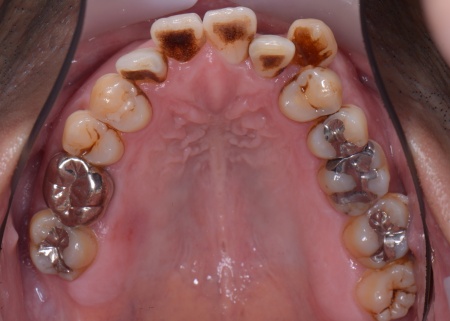

40代男性 乱れた歯並びと重度歯周病をワイヤー矯正と歯周再生療法で治療した症例

拝見したところ、上下の歯は、ずれたりねじれたりしてデコボコに生えており、著しく歯並びが乱れていました。

またレントゲン撮影をして確認すると、右上前歯は顎の骨の中に埋まっている骨性埋伏(こっせいまいふく)の状態でした。

今回のケースでは、左上下の奥歯各1本(第3大臼歯)、右下の奥歯1本(第3大臼歯)、左上下と右下の奥歯各1本(第1小臼歯)の計6本の抜歯が必要です。

骨に埋まっている右上前歯は引っ張り出すことができないため、隣の歯である右上奥歯(第1小臼歯)を代用歯として機能させる方法を選択しました。

また、奥歯の噛み合わせは正常だったことから、それを維持しながら歯並びを整えるために以下の方法を採用します。

・上顎には歯の裏側に固定装置「トランスパラタルアーチ」を装着する